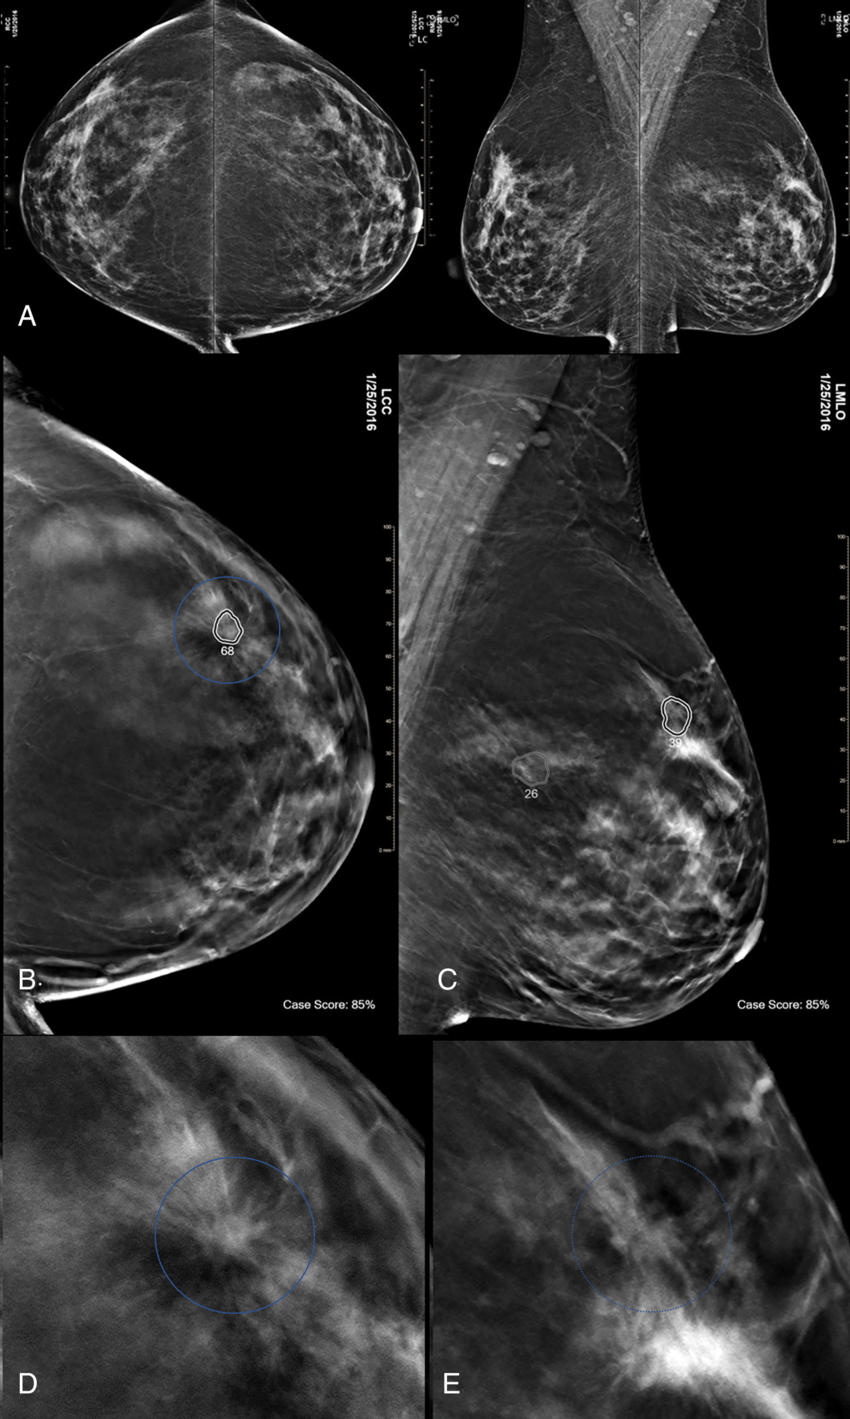

Figure 4. Images in a 74-yearold woman at screening with combination digital mammography (DM) and digital breast tomosynthesis (DBT).

High-res (TIF) version

Figure 5. Images in a 47-yearold woman at screening with combination digital mammography (DM) and digital breast tomosynthesis (DBT).